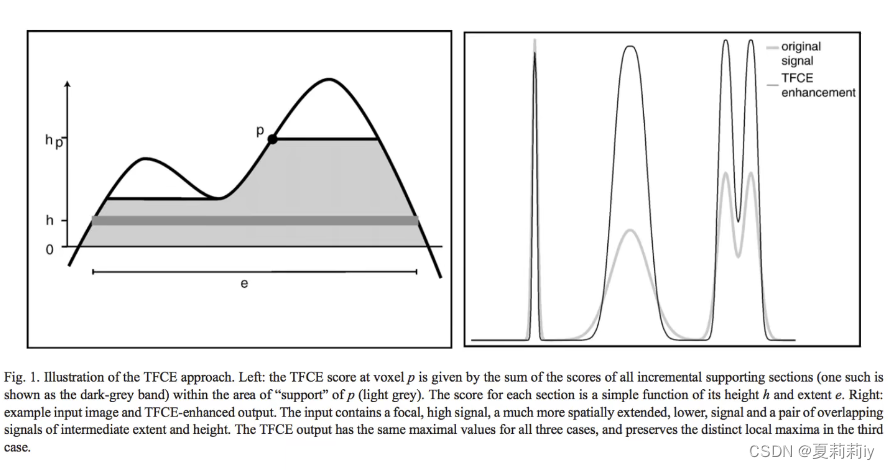

⑥Threshold-Free Cluster Enhancement(TFCE):